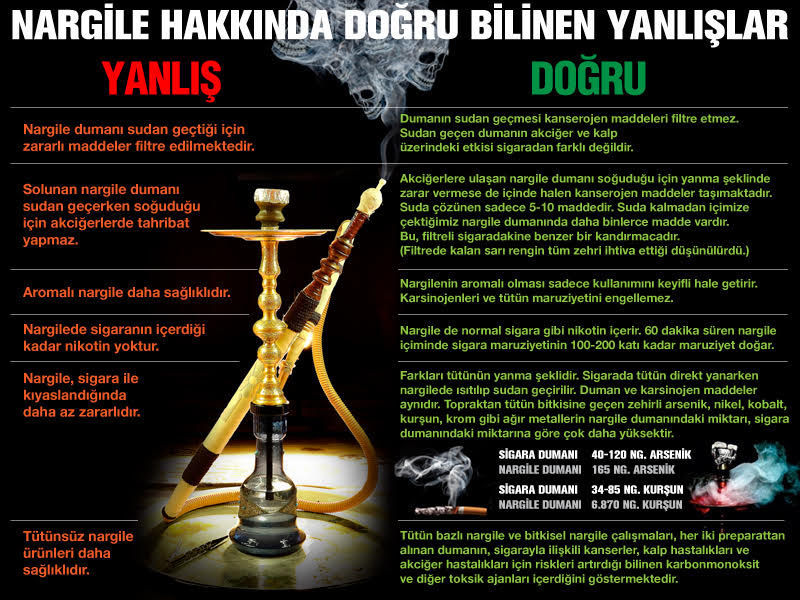

Aromalı ve meyveli şekilde pazarlanan bu ürünlerde "zararsız" ya da "sigaradan daha az zararlı" olduğu imajı verilmeye çalışıldığını aktaran Savaşçı, sözlerine şöyle devam etti: "Bilimsel araştırmalar, durumun hiç de böyle olmadığını göstermektedir. Nargilenin çok fazla zararlı olmasının nedeni ise, kobalt, kurşun ve nikel içeriyor olmasından kaynaklanmaktadır. Sigarada 30-80 mg kurşun var ama nargilede bu oran 68-70 mg olarak katlandıkça katlanmaktadır.

Sigara dumanında 45-125 mg arsenik mevcut iken nargilede bu zararlı arsenik, 165 mg olarak bulunmaktadır. Bir nargile seansı 100 sigara içmeye eşdeğer toksik etki yapmaktadır."